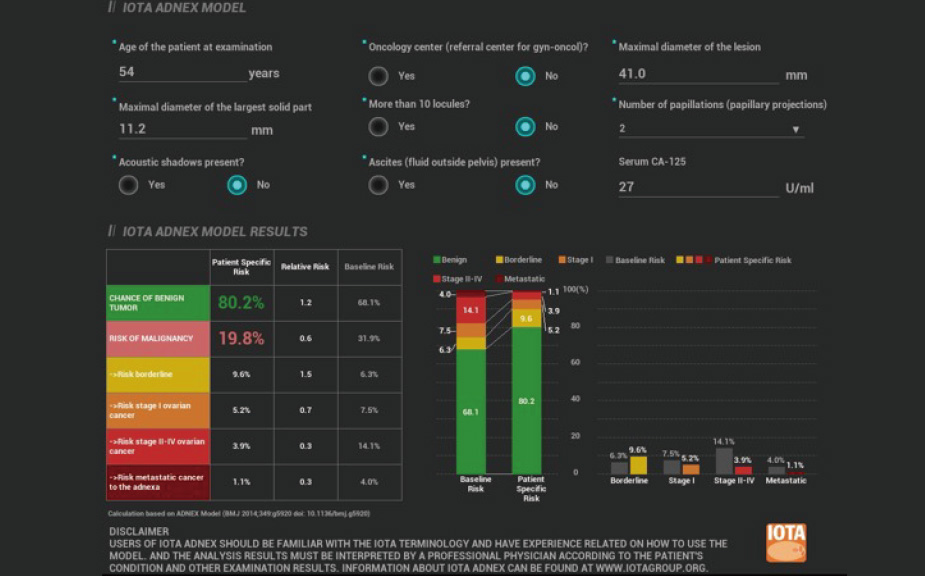

Intelligenza completa orientata allo scenario clinico

L'innovativa soluzione Smart Scene 3D consente l'identificazione automatica delle caratteristiche dei tessuti e fornisce una diagnosi specifica per i diversi distretti di esame durante l'intera procedura. Questa innovazione aumenta lŌĆÖaccuratezza e la sicurezza diagnostica, migliorando lŌĆÖefficienza.